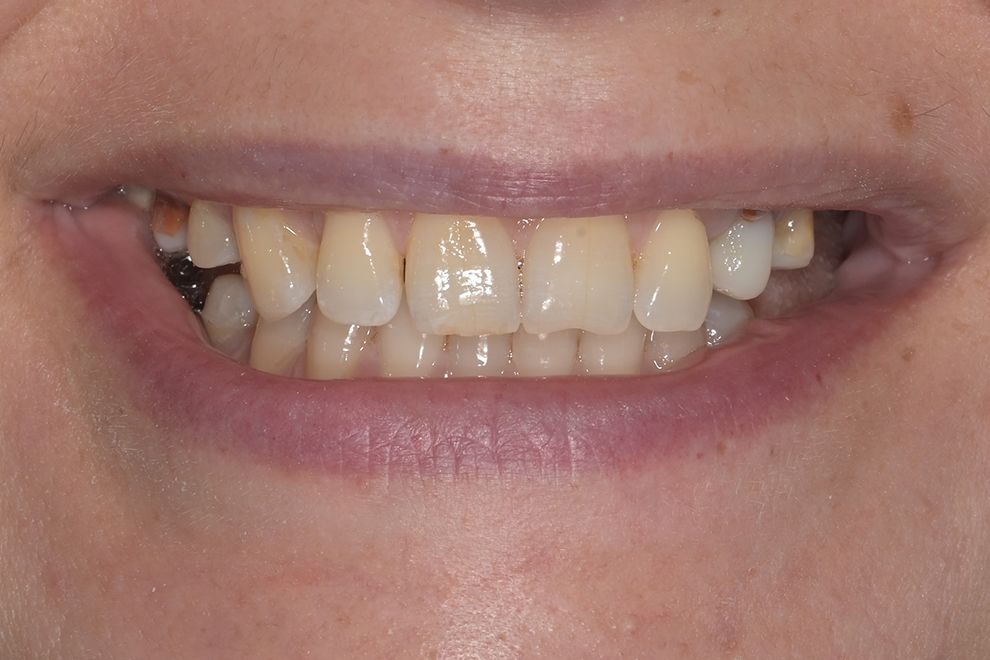

до и после